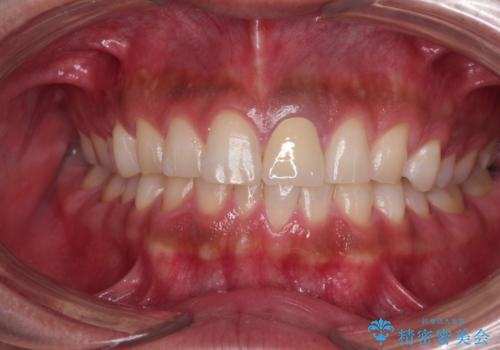

- 神経を取り除いたことで変色した前歯を気にして来院された患者様です。

根管治療はやり直さずに、ファイバーポストを使用した土台を植立してオールセラミッククラウンにて補綴することとしました。

神経を取り除いた歯は時間とともに変色してきます。

クリーニングやホワイトニングでは改善できないため、オールセラミッククラウンなどによる補綴治療が必要となります。